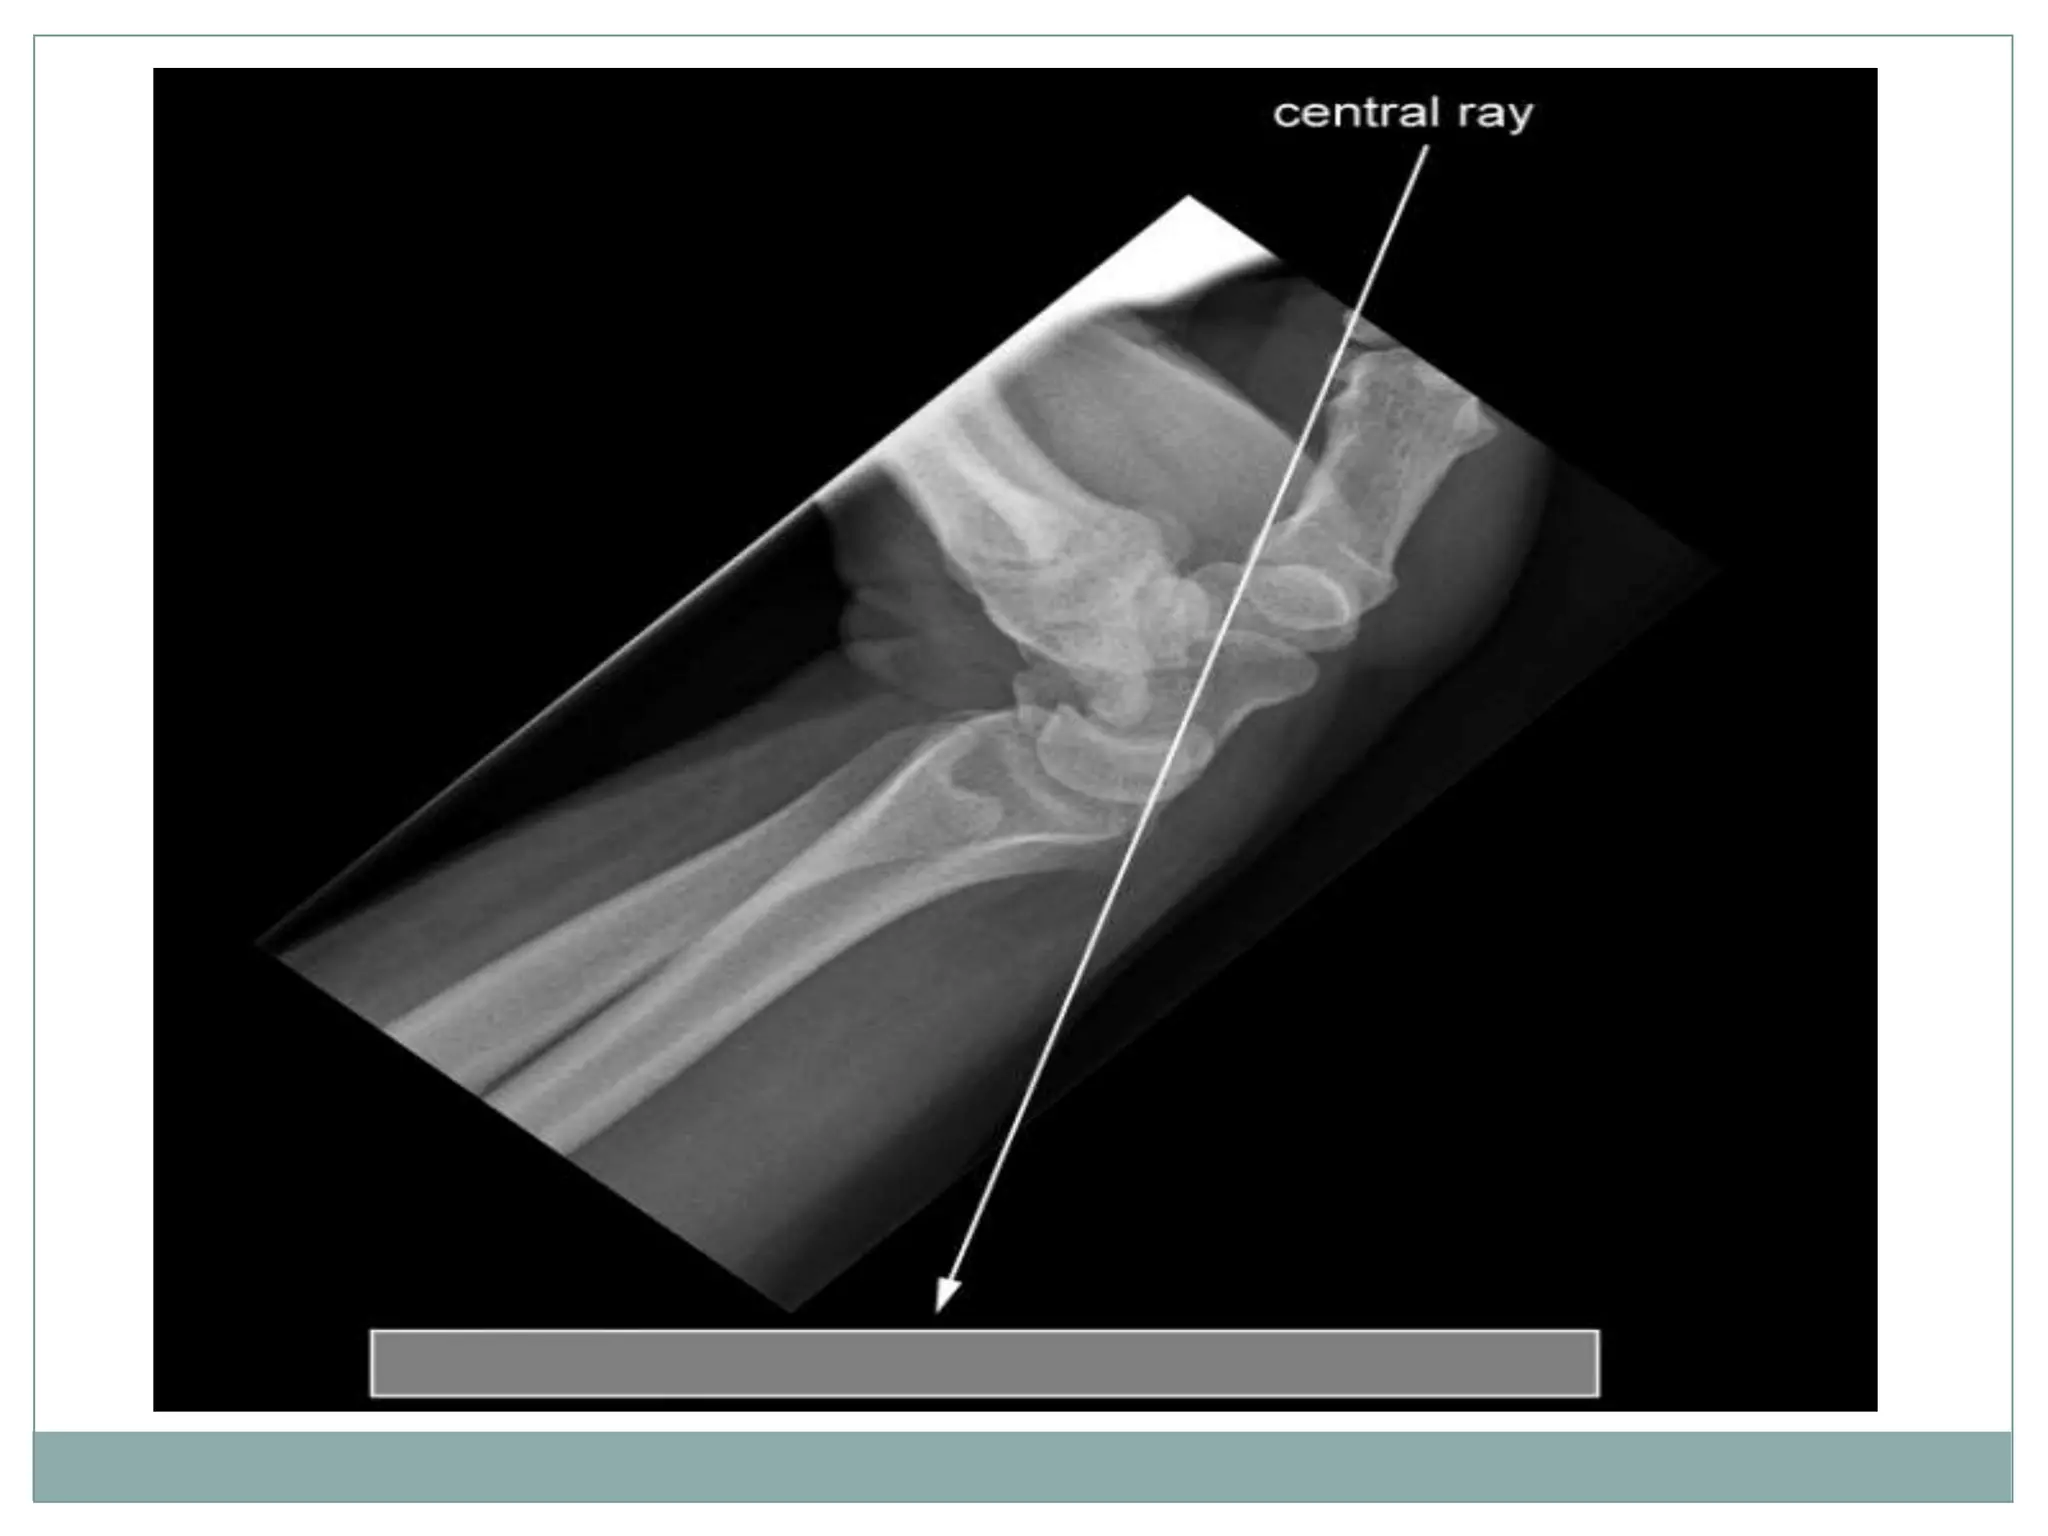

Patient Position

 The patient is seated

alongside the table.

 The detector is placed on top

of a plastic block approximately

8 cm high

 The lower end of the forearm

rests Against the edge of the

block, with the Wrist adducted

and dorsiflexed to 135º

 This position is assisted using

a traction bandage held by the

patients other hand

Centring point

 Mid carpal region

 The central ray is vertical and will be

centered to the midpoint of the

dorsiflexed wrist

Collimation

 Laterally to the skin margins

 Dorsal to the skin margins

 Ventral to the carpometacarpal joint

Axial projection

Orientation

 Portrait

Detector size

18 cm x 24 cm

Exposure

50-60 kVp

3-5 mAs

The image should demonstrate clearly the pisiform and the

hook of the hamate medially and the tubercle of the scaphoid

and the tubercle of the trapezium laterally.

Patient Position  Thepatient is seated alongside the table.  The detector is placed on top of a plastic block approximately 8 cm high  The lower end of the forearm rests Against the edge of the block, with the Wrist adducted and dorsiflexed to 135º  This position is assisted using a traction bandage held by the patients other hand

Centring point  Midcarpal region  The central ray is vertical and will be centered to the midpoint of the dorsiflexed wrist Collimation  Laterally to the skin margins  Dorsal to the skin margins  Ventral to the carpometacarpal joint Axial projection

Orientation  Portrait Detector size 18cm x 24 cm Exposure 50-60 kVp 3-5 mAs

The image shoulddemonstrate clearly the pisiform and the hook of the hamate medially and the tubercle of the scaphoid and the tubercle of the trapezium laterally.